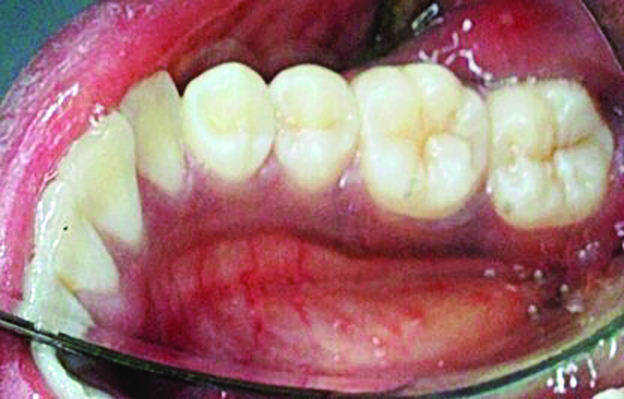

Table 1 presents descriptive statistics for the demographic characteristics of the participants: 83.33% of the study population were aged 18 to 24 years, while 16.66% were aged 25 to 30 years, and 20% of the participants were male while 80% were female, indicating a skewed distribution. Figure 4 through Figure 6 illustrate lingual AG of a representative male subject, and Figure 7 through Figure 9 depict that of a female subject. The mean, standard deviation, mode, median, and extremes for all the mandibular permanent teeth are recorded in Table 2. The extreme measurements were in the range of 0 mm to 10 mm, considering all teeth and subjects. The width of lingual AG varied with each tooth, with the mandibular first molar having the widest average width (6 mm ± 1.3 mm) followed closely by the second molar (5.8 mm ± 1.2 mm). The central incisors (0.5 mm ± 0.5 mm) showed the narrowest zone along with the highest maximum number of teeth without detectable AG (Table 3). The width of AG did not significantly differ between the sexes (Table 4). The overall indicative schematic of lingual AG is shown in Figure 10 and Figure 11.

Fig 7. Lingual attached gingiva in a female subject: Fig 7 = left side, Fig 8 = middle, Fig 9 = right side.

Figure 7

Fig 8. Lingual attached gingiva in a female subject: Fig 7 = left side, Fig 8 = middle, Fig 9 = right side.

Figure 8

Fig 9. Lingual attached gingiva in a female subject: Fig 7 = left side, Fig 8 = middle, Fig 9 = right side.

Figure 9